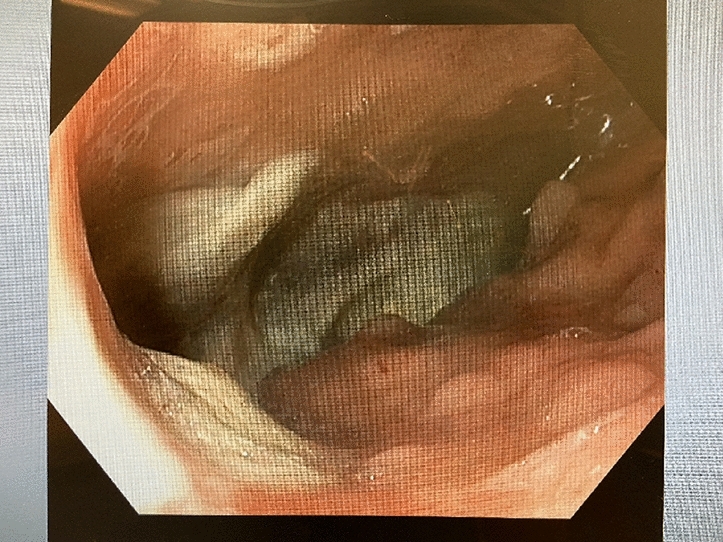

Methods: We present a 72-year-old male with prior radical cystectomy and neobladder creation complicated at the time by neobladder-cutaneous fistula and wound infection requiring revisional surgery and incisional hernia repair with mesh. He developed a large recurrent incisional hernia and underwent open hernia repair with bilateral anterior component separation, extensive lysis of adhesions, removal of prior mesh, and placement of a biologic mesh (Strattice™ RTM) in an underlay and onlay fashion. Intraoperatively, the defect measured 20 cm long by 14 cm wide. Postoperatively, he was treated for neobladder infection and CT cystogram found no extravasation from the neobladder. He presented to the emergency department 6 weeks after surgery with spontaneous partial midline wound dehiscence, with exposure of the onlay mesh and drainage of clear fluid, which was confirmed to be urine by fluid creatinine level. Repeat CT scan demonstrated a filling defect at the anterior wall of the neobladder with contrast leaking into a contained collection interposed between the anterior abdominal wall and the underlay mesh, extending superiorly between the small bowel loops and dehiscence of the midline abdominal wound. The patient was treated with a course of antibiotics and indwelling Foley catheter and bilateral nephrostomy tubes for urine diversion.

Results: Three months later, repeat CT cystogram demonstrated resolution of the leak and the nephrostomy tubes and Foley catheter were removed. The patient has continued daily wound care with significant reduction in size of the midline wound and increasing granulation tissue around the onlay mesh. He has not required further admissions to hospital and there has been no hernia recurrence so far.

Conclusion: In the appropriate setting, contaminated biologic mesh after surgery may be treated with medical management with adequate wound closure, avoiding the need for surgery and mesh explantation.